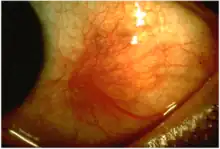

Scleritis is a serious inflammatory disease that affects the white outer coating of the eye, known as the sclera. The disease is often contracted through association with other diseases of the body, such as granulomatosis with polyangiitis or rheumatoid arthritis. There are three types of scleritis: diffuse scleritis (the most common), nodular scleritis, and necrotizing scleritis (the most severe). Scleritis may be the first symptom of onset of connective tissue disease.[1]

- Redness of the sclera and conjunctiva, sometimes changing to a purple hue

The pain of episcleritis is less severe than in scleritis.[4] In hyperemia, there is a visible increase in the blood flow to the sclera (hyperaemia), which accounts for the redness of the eye. Unlike in conjunctivitis, this redness will not move with gentle pressure to the conjunctiva.